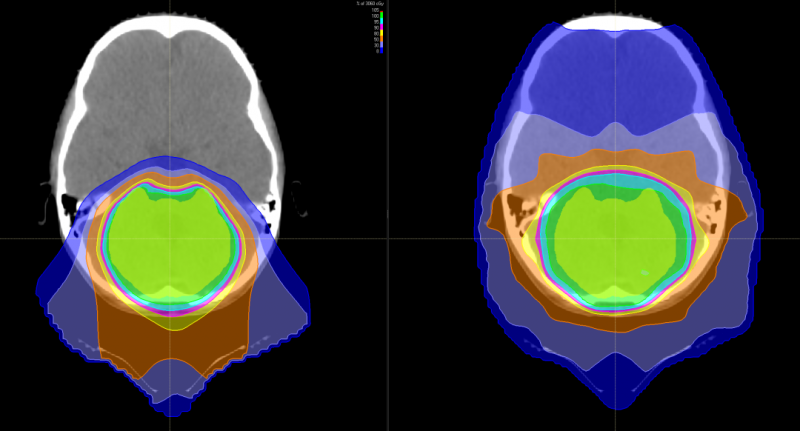

图中患者的脑部扫描显示质子(左)如何专门针对肿瘤,而对周围组织和结构的辐射最小,传统的光子辐射(右)会损坏周围的组织和结构。

上图为髓母细胞瘤对全脑全脊髓照射剂量的分布图比较,传统放疗会对身体造成大范围的损害,波及脊柱周边的脏器,而质子治疗剂量分布图,脊髓周边的照射剂量机乎为零,不会造成损害及副作用。